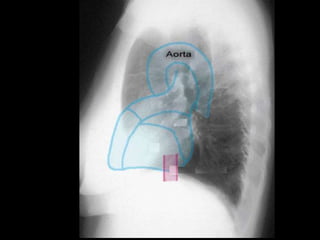

RADIOGRAFIA

• Radiografía normal

• Radiografía patológica

– Ensanchamiento mediastinal

• Técnica radiográfica

• Estructuras normales de tamaño o distribución atípica

• Estructuras vasculares

• Tumores

RADIOGRAFIA • Radiografía normal •Radiografía patológica – Ensanchamiento mediastinal • Técnica radiográfica • Estructuras normales de tamaño o distribución atípica • Estructuras vasculares • Tumores